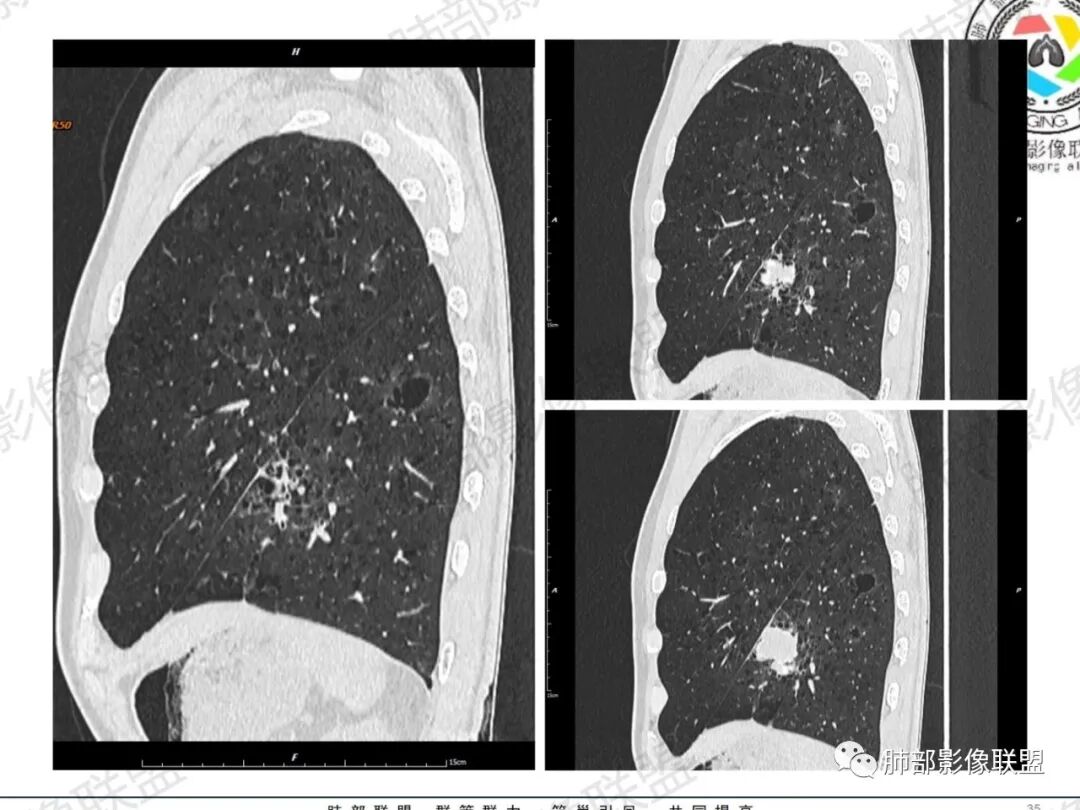

琦遇:恶性没有问题,肺气肿底子、病灶分叶、少许毛刺、叶间胸膜凹陷、部分边缘可见清晰的GGO、胸膜牵拉凹陷、局部胸水、近端支气管截断、部分支气管被推移、占位效应明显、强化特点为不均匀强化、内部有少许沼泽样低强化区,强化部分轻中强化为主、余肺可见转移性结节、左肺上叶似为囊腔型腺癌一枚,肿瘤标志物提示非小、神经内分泌,综合分析考虑大神泌、腺癌、腺鳞癌、鳞癌  同时左肺上叶囊腔型腺癌  肺转移

蕊:中老年男性,吸烟史,肺气肿背景,左肺上叶类圆形肿块影,边界清晰,边缘凹凸不平,有分叶,支气管进入阻断,临近胸膜栽赃,整体病灶膨隆,局部周围可以清晰ggo,临近叶间裂内凹,轻度强化,并可见多个低密度区,坏死可能,界线不清;肺内多结节,边缘光滑,考虑恶性伴转移,鳞癌、腺癌

小锁:中老年男性,肺气肿背景,右胸背疼痛1周。CEA、NSE、CYFRA—211升高。左上肺混合磨玻璃结节,边界清楚,内见较多空泡。左下肺肿块,边缘清楚,深分叶,有血管和支气管进入,胸膜凹陷。另两肺多发圆形小结节。考虑双发原位癌,左上肺腺癌,左下肺大神泌或腺鳞癌可能,肺内转移。

蓝天白云:中年男性,肺气肿背景,左肺下叶肿块,边缘膨隆,有分叶,内有湖泊样坏死,有轻中度强化,局部胸膜栽赃,收缩力不强,周围见肺气肿征象。左肺上叶混合磨玻璃影,边界清楚,考虑都是恶性,左上肺iac,左下肺腺鳞癌,或大细胞肺癌可能。两肺多发结节,考虑转移

周太狼:中年男性,吸烟、高血压史,肿瘤指标升高,肺气肿背景下,左肺下叶肿块影,分叶、膨隆、未跨叶裂,支气管截断,不均匀强化。另双肺多发结节及磨玻璃影,左肺上叶混合磨玻璃,内可见多发空泡影。整体考虑恶性,肺癌伴肺内转移,左下肺鳞癌?神经内分泌癌?左肺上叶囊腔腺癌?

LCNEC最常见的影像特征包括:(1)肿块发生部位:周围型肺癌为主,少数发生于肺中央。(2)肿块大小及形态。因肿瘤细胞生长迅速常形成较大肿块,因此其体积一般较大,直径常在3~10cm范围内,病灶常为不规则形软组织肿块。(3)肿块边界。多数学者报道大多数肿块边界清晰,边缘呈分叶状,毛刺征及“胸膜凹陷征”少见,认为与该病对周围组织浸润较轻及较少产生纤维瘢痕组织牵拉有关联。(4)肿块密度、强化特点及代谢情况。据文献报道,该类肿瘤因体积较大CT上常见软组织肿块,且多数密度不均匀,内见囊变坏死区,增强后呈轻或中度不均匀强化(可见强化者占75.7%),认为其强化特点与其内部肉眼可见坏死灶和肿瘤较大直径有关。(5)伴随症状及远处转移。该病恶性程度高,侵袭性强,常侵犯邻近结构,如胸膜、心包、邻近骨质或纵隔内组织等,易出现纵隔淋巴结转移,部分发生肺内及远处转移,少数早期可出现广泛远处转移。